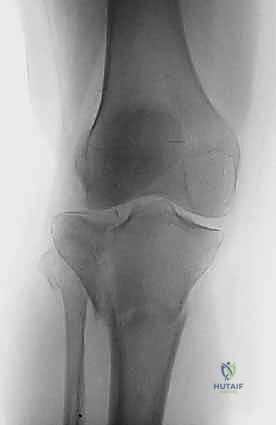

2. التصوير الإشعاعي (X-rays)

الخطوة الأولى هي التقاط صور أشعة سينية من عدة زوايا (أمامية خلفية، وجانبية). تعطي الأشعة السينية فكرة عامة عن وجود الكسر وموقعه، لكنها غير كافية لتقييم الكسور ثنائية اللقمة المعقدة.